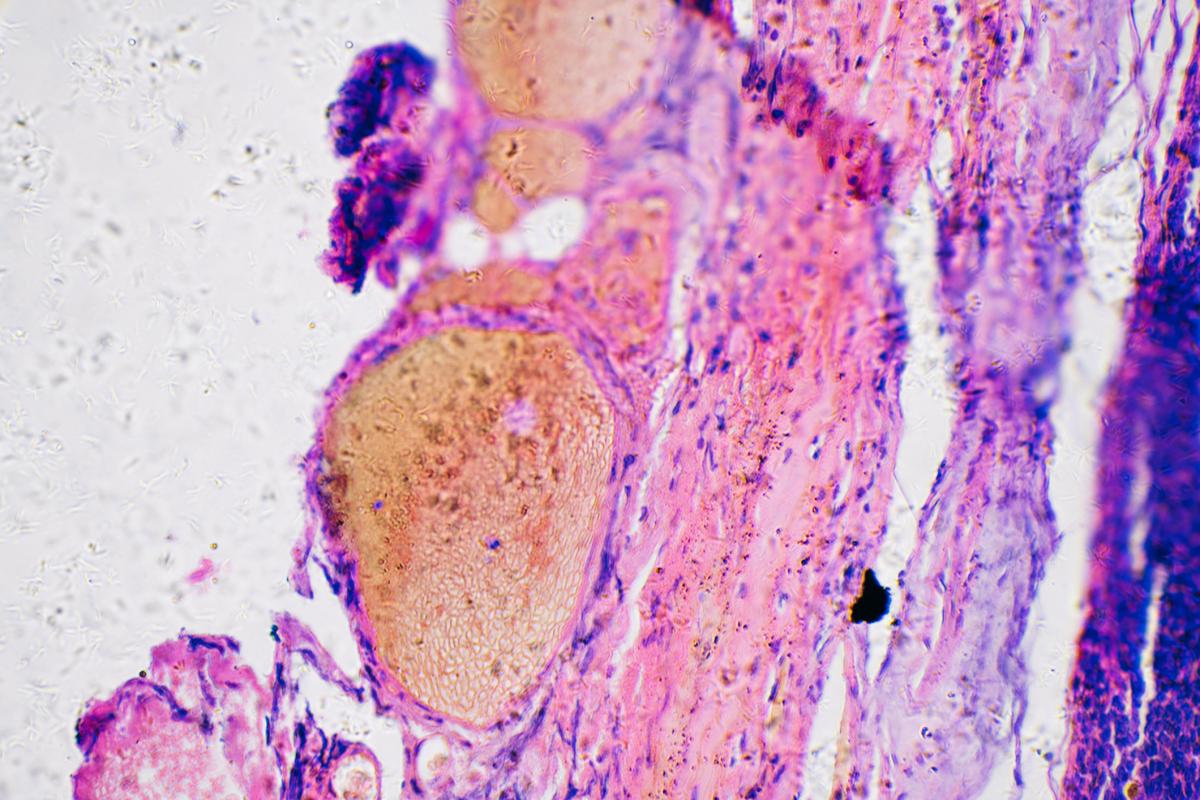

Se trata de Keytruda (inmunoterapia pembrolizumab), un exitoso anticuerpo monoclonal humanizado que sirve de ayuda a las células inmunitarias para destruir las células cancerosas.